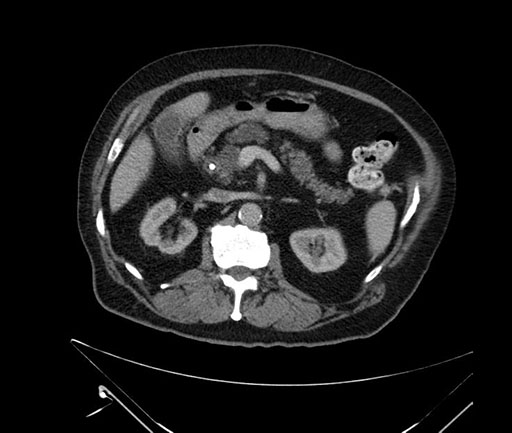

Imaging Analysis

Look through the patient's CT scan to identify any areas of concern for the necessary procedure.

Based on your CT findings, which issue(s) would give reason for "planned slowing down moment(s)" in this case?